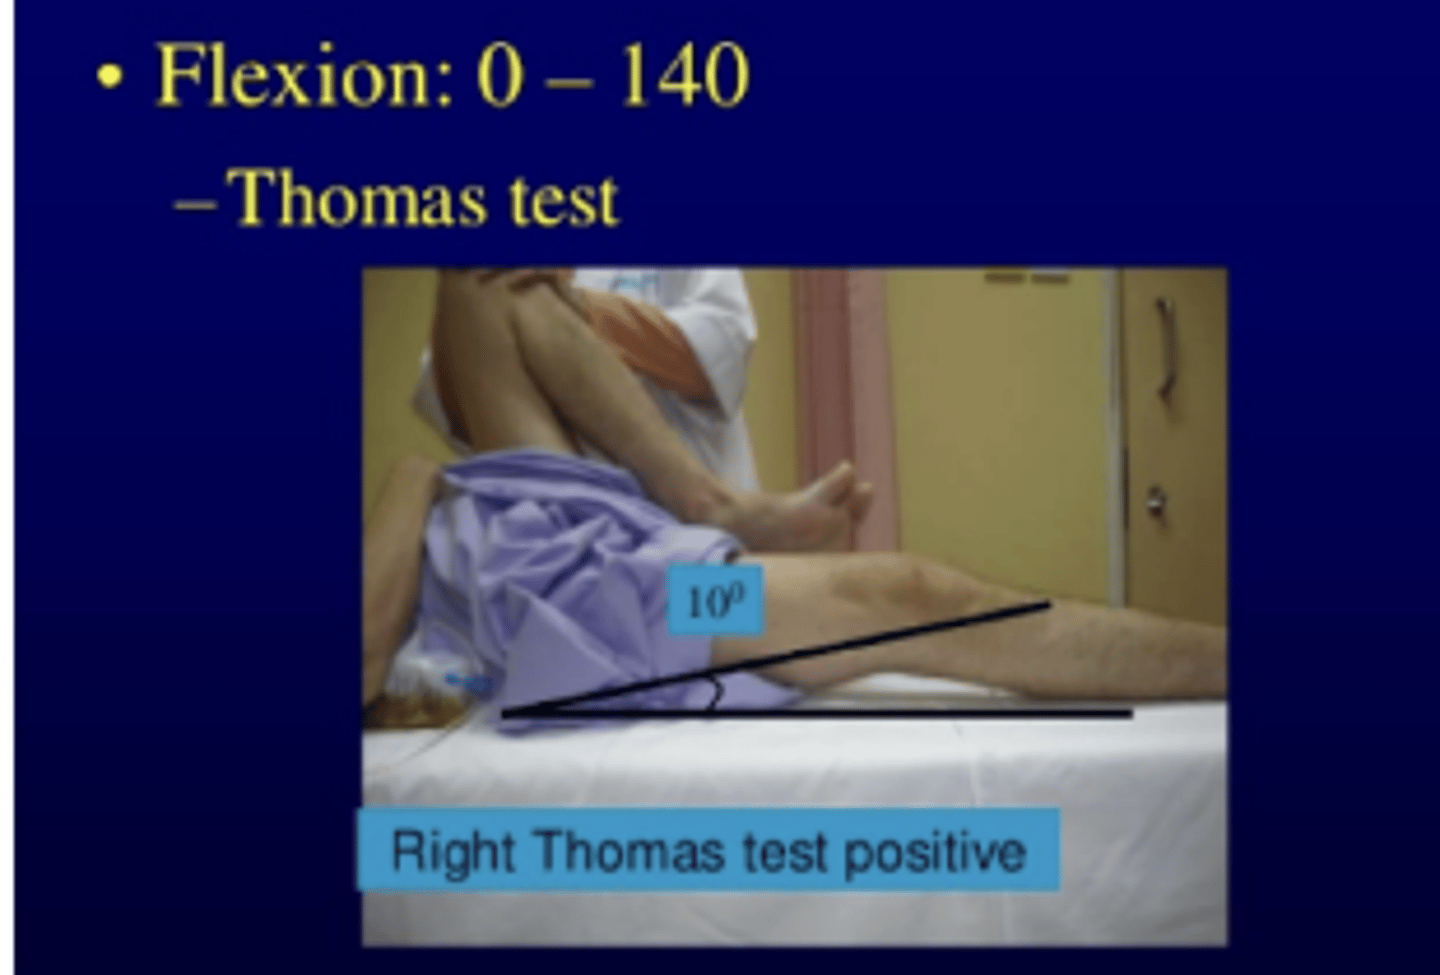

Thomas Test

positive= femur lifted 10 degrees off of the bed

Tests for: Internal Coxa Saltans, tight hip flexors/contracture